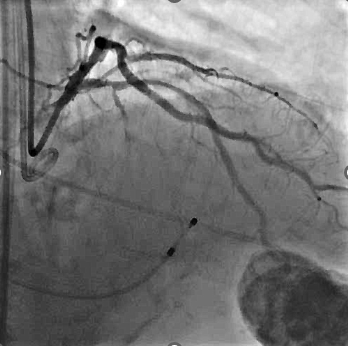

冠脉造影及介入治疗:将ACIST CVi血管造影注射系统调整至冠脉造影模式,完善冠脉造影。结果示:LM未见明显狭窄,LAD近端80%狭窄,严重钙化,IVUS可见360°钙化。回旋支少量斑块浸润,右冠状动脉30-40%狭窄。决定处理LAD,由于患者存在严重钙化,使用Shockwave球囊预处理打开钙化,后植入3.0*24mm +3.5*24mm药物涂层支架,效果满意。